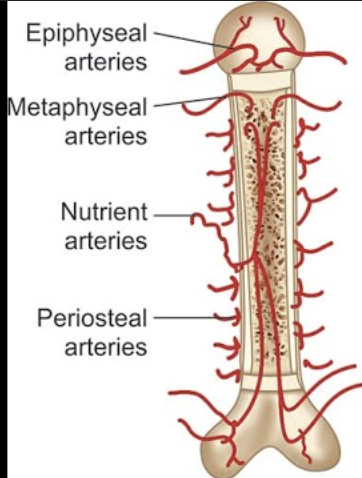

Arteries

Periosteal Arteries (periosteum)

Nutrient Arteries (diaphysis)

Metaphysical Arteries (metaphysis)

Epiphyseal Arteries (epiphysis)

Periosteal Arteries

Enter diaphysis through perforating canals, supply periosteum

Nutrient Artery

Large artery passes through compact bone into medullary cavity; divides into distal & proximal branches

Supply inner diaphysis & red bone marrow

Metaphyseal Arteries

Supply RBM & tissue to metaphysis

Epiphyseal Arteries

Supply RBM & tissue to epiphysis

Veins

Carry blood away from the bone

Different types of veins (nutrient, epiphyseal, metaphyseal, periosteal) accompany respective arteries